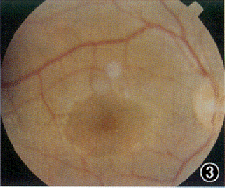

患者男,21岁。因双眼视力逐渐下降7年,蛋白尿、听力下降4年,高血压1年,于1998年5月入我院肾病内科诊治。既往无眼部疾病史。母亲曾有“肾盂肾炎”病史,已治愈。其他家族病史不详。体检:血压160/110 mm Hg(1 mm Hg=0.133 kPa);轻度Cushing征外貌,余无异常。眼部检查:裸眼视力右眼0.2,左眼0.4;矫正视力右眼0.7(-11.0 DS +0.75 DC×90°),左眼0.7(-10.0 DS +0.75 DC×90°);双眼晶状体前表面中央区局限性前突,呈锥形,囊膜下可见小斑点状白色混浊(图1,2);双眼视盘色泽正常,边界清晰,视网膜血管大致正常,后极部黄斑区周围可见散在的黄白色点状颗粒,黄斑中心窝反光可见(图3,4);眼底血管荧光造影检查示双眼黄斑拱环结构破坏。辅助检查:(1)耳科电测听:双耳对称性感音神经性耳聋(中、重度);(2)肾活检报告:光镜示系膜增殖性肾小球肾炎改变(重度);免疫荧光检查为阴性;电镜示肾小球基底膜广泛变厚、劈裂;(3)眼电图、视网膜电图未见异常表现;(4)尿蛋白50 mg/L,血尿素氮 7.2 mmol/L, 血清肌酐185.6 μmol/L。诊断:Alport综合征。

图1 右眼晶状体前表面中央区局限性前突,呈锥形,囊膜下可见小斑点状白色混浊(箭头) 图2 左眼晶状体前表面特征同图1 图3右眼视盘色泽正常,边界清晰,视网膜血管大致正常,后极部黄斑区周围可见散在的黄白色点状颗粒,黄斑中心凹反光可见 图4 左眼眼底特征同图3